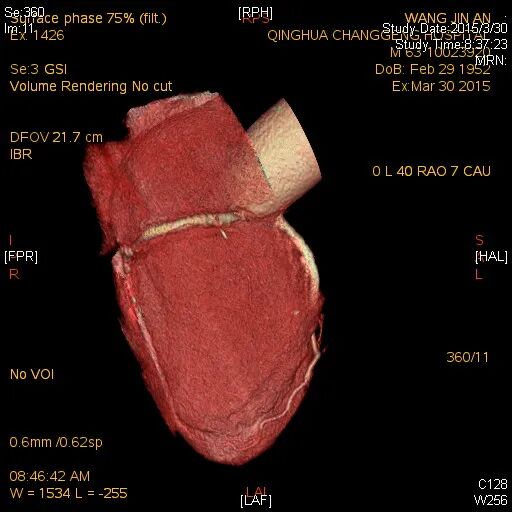

检查结果-CTA